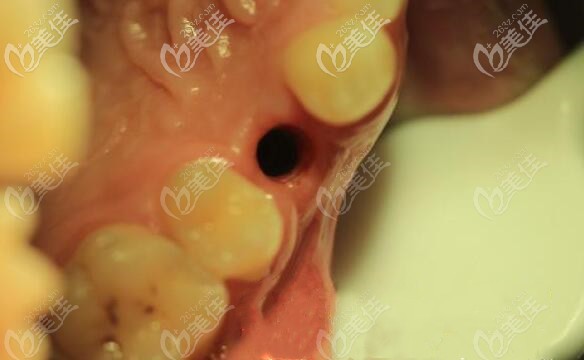

手術(shù)時(shí)間也就把半個(gè)小時(shí)就完成了,當(dāng)天為顧客戴臨時(shí)冠,

后經(jīng)過六個(gè)月的觀察后發(fā)現(xiàn)修復(fù)效果良好,從圖片可以看出哪個(gè)是種植牙嗎?